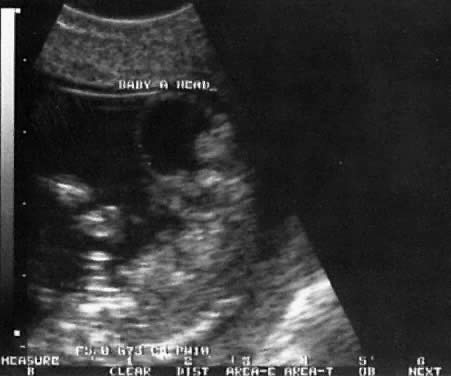

1. Holoprosencephaly: In this condition, the cerebral hemispheres do not separate; a single ventricle is noted, and hypotelorism is a characteristic finding. Fetal karyotype is abnormal in 50% of fetuses with holoprosencephaly, and trisomy 13 is the most frequent chromosomal abnormality. The diagnosis may be made in the latter part of the first trimester with the use of high-frequency vaginal ultrasound (Fig. 24).

Fig. 24. Echogram of the head (HEAD) of one fetal twin at 13 weeks' gestation, showing holoprosencephaly.